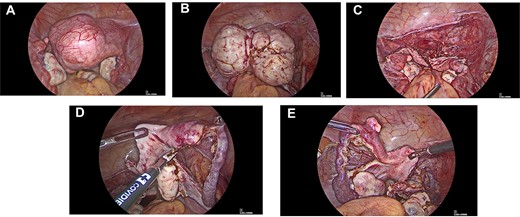

A 28-year-old nulligravida presented to the emergency with urinary retention and abdominal pain for 2 days. She had primary amenorrhea for which workup was done at age of 16 years and diagnosis of MRKH syndrome was made. She got married at age of 20 years and was sexually active since then. She was catheterized in emergency and 2 liters of urine was drained. On examination huge abdomino-pelvic mass of around 20 weeks, nodular, hard in consistency could be palpated. Vaginal length was 7 cm with no history of sexual dissatisfaction or vaginoplasty. Magnetic resonance imaging (MRI) suggested multiple leiomyomas arising for both uterine rudimentary horns (Fig. 1). lntra-operatively, 10 × 9 × 8 cm bilobed hard myoma arising from right uterine horn with one of the lobe deeply embedded in lateral pelvic wall seen and left uterine horn seen to be harboring multiple small fibroids. Both tubes and ovaries were normal. Leiomyoma was removed by traction and countertraction and keeping ureters under vision (Fig. 2A–C). Bilateral rudimentary uterine horns along with median raphe were excised and removed to prevent recurrence (Fig. 2D and E). Post-operative period was uneventful. Histopathology report was suggestive of leiomyoma and rudimentary uterine tissue.

(A) Intra-operative images showing leiomyoma arising from right uterine horn. (B) Intra-operative images showing myoma dissected out of lateral pelvic wall. (C) Intra-operative images showing Mullerian buds after removal of myoma. (D) Intra-operative images showing removal of right uterine bud. (E) Intra-operative images showing small myoma in connective tissue between fallopian tube and uterine horn.